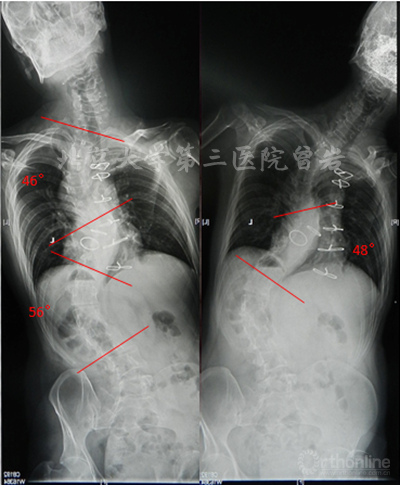

CT(图7):显示脊柱侧后凸畸形,腰骶段椎管扩大,椎体扇贝样改变,椎弓根发育异常,L5峡部不连。

图7